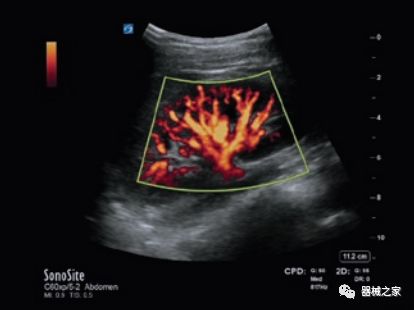

GE Healthcare用于胎儿超声的胎儿心脏和血管分析软件,在Voluson E10上提供,有助于在不到三分钟的时间内评估胎儿的心脏形状,大小和收缩性。称为辐射流的功能以三维视图显示血流。它还可以帮助显示缓慢流动的血液,例如神经血管循环。

Voluson E10